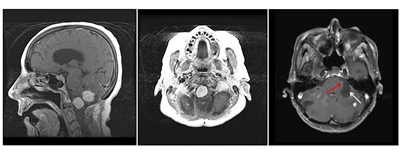

Figure 2. Hemangioblastomas are the most common disease manifestation in patients with von Hippel-Lindau disease. The left panel shows a sagittal view of brainstem and cerebellar lesions. The middle panel shows an axial view of a brainstem lesion. The right panel shows a cerebellar lesion (red arrow) with a dominant cystic component (white arrow).